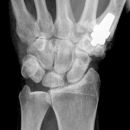

Bennett Fraktur

Bennett Fraktur mit geringer Dislokation